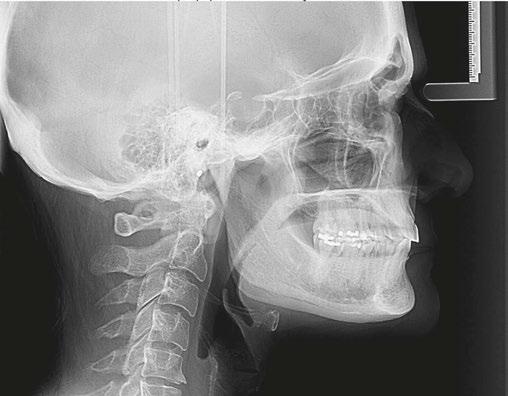

12: A lateral cephalometric radiograph of a patient with excessive interlabial gap (radiograph was taken with lips postured closed). The excessive vertical has resulted in a long history of forward head posture as she pushes to close her lips. She has developed arthritis of the spine and spondylisthesis (AP vertebral instability) secondary to her consistent forward head posture. Image captured using Dolphin software (www.dolphinimaging.com)

Figure 16 (left): The facial photo of the patient shows her making excessive efforts to get her lips to touch, elongating the upper lip and turning the vermillion inwards. The mentalis muscle is extremely active elevating the lower lip. She also has a forward head posture.

Figure 17 (right): The lateral cephalometric radiograph, taken in repose, shows the extent of the interlabial gap, anterior open bite, and small airway. Note the silicone chin implant which was an attempt to ineffectively correct her severe skeletal discrepancy. Image captured using Dolphin software (www.dolphinimaging.com)

A 39-year-old female with a significant open bite presents to the oral and maxillofacial surgeon’s office on referral from the orthodontist for orthognathic surgery. She has a long history of pain and dysfunction. (Figures 15-17)